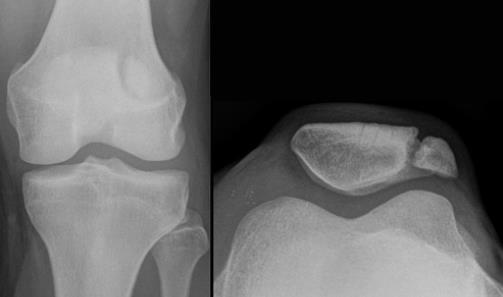

U 27-letniej chorej z negatywnym wywiadem urazowym w przeszłości, 3 godziny po urazie bezpośrednim stawu kolanowego doznanym w wyniku upadku na asfaltowe podłoże podczas jazdy na rolkach i z obrazem Rtg jw., najkorzystniej jest:

Pytanie 55